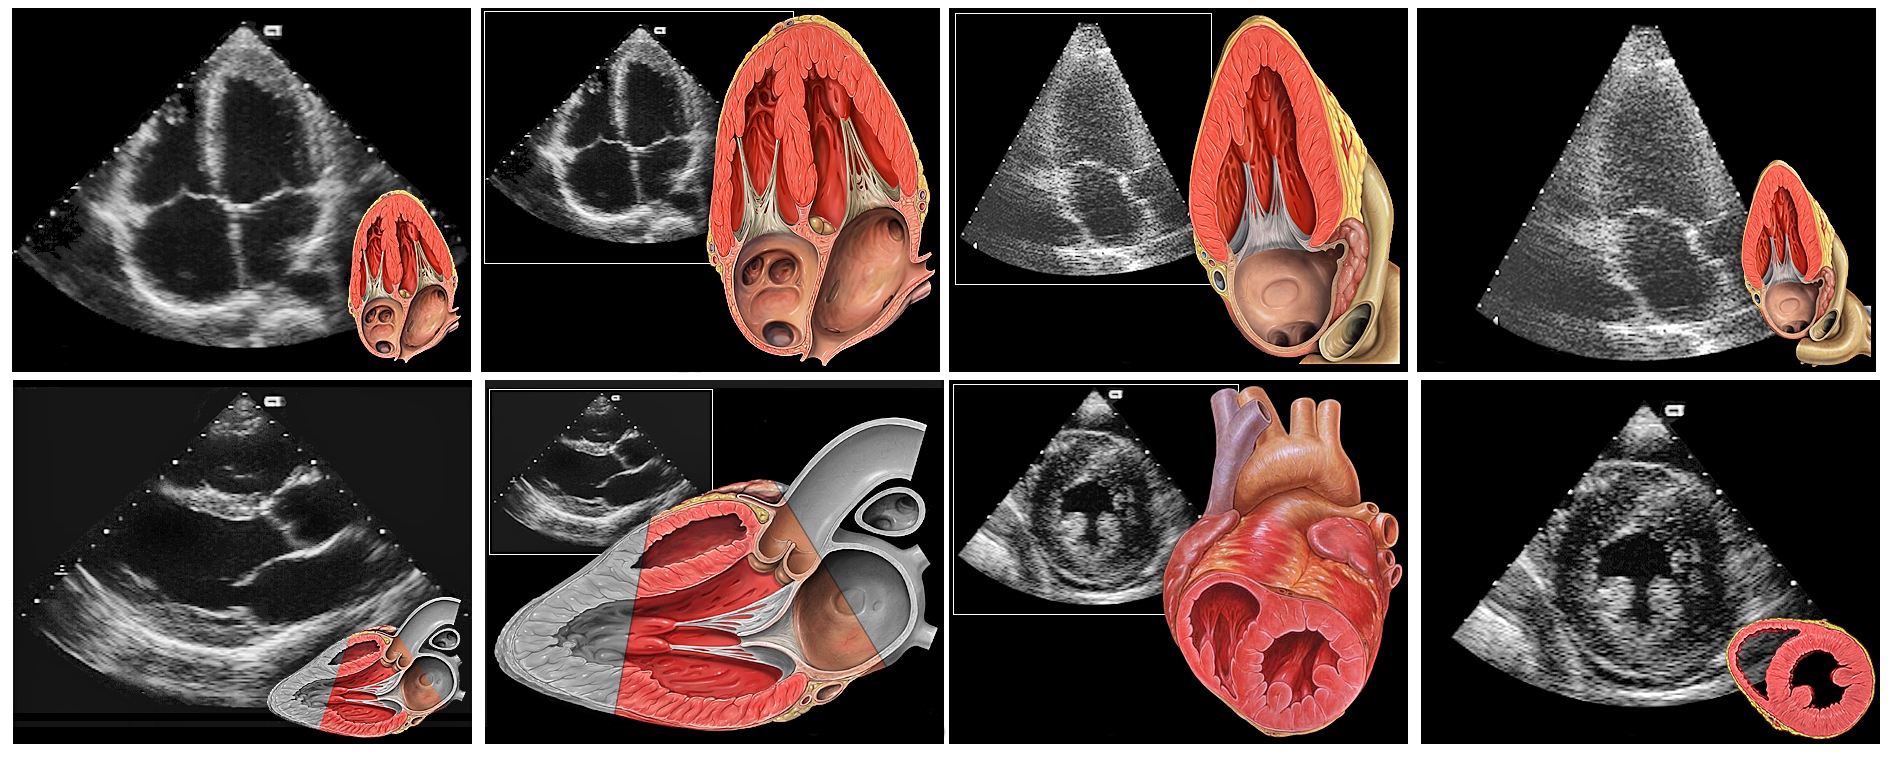

| Sonarbilder und Zeichnungen der Herzklappen aus verschiedenen Perspektiven |

![]() |

| Patrick J. Lynch, Creative Commons Attribution 2.5 Generic |

| Gezeigt werden verschiedene Schnittebenen durch das Herz jeweils als farbiges Schema neben der entsprechenden schwarzweißen echokardiografischen Abbildung. |